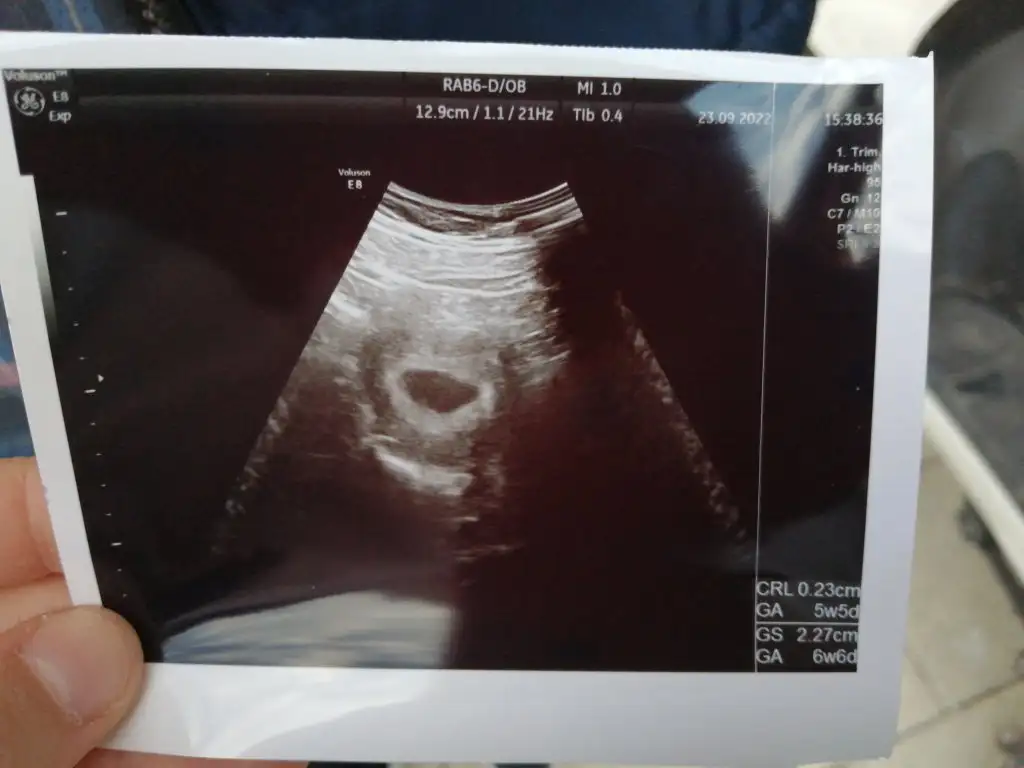

Her şey normalmi diye sordum normal dedi Tüp bebek tedavisi gördüğüm hastanenin hemşiresine de atdım gözünüz aydın kese gözükmüş dedi

Eki Görüntüle 3134585

Canim cihazdan cihaza bile fark ediyor gonlunu ferah tut. Ben kendi doktorumda kese gormustum 2 gun sonra ilac yazdirmaya gittigim doktor hem bebegi gordu hemde kalp atisi baslamis dedi.